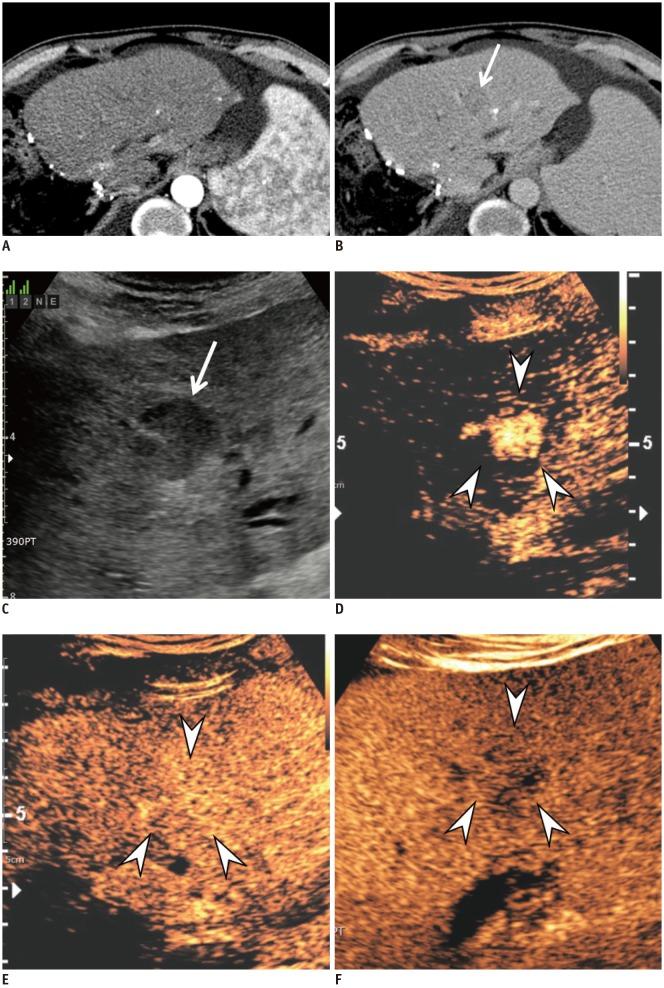

Hepatocellular carcinoma (HCC) can be noninvasively diagnosed on the basis of its characteristic imaging findings of arterial phase enhancement and portal/delayed "washout" on computed tomography (CT) and magnetic resonance imaging (MRI) in cirrhotic patients. However, different specific diagnostic criteria have been proposed by several countries and major academic societies. In 2018, major guideline updates were proposed by the Association for the Study of Liver Diseases, European Association for the Study of the Liver (EASL), Korean Liver Cancer Association and National Cancer Center (KLCA-NCC) of Korea. In addition to dynamic CT and MRI using extracellular contrast media, these new guidelines now include magnetic resonance imaging (MRI) using hepatobiliary contrast media as the first-line diagnostic test, while the KLCA-NCC and EASL guidelines also include contrast-enhanced ultrasound (CEUS) as the second-line diagnostic test. Therefore, hepatobiliary MR contrast media and CEUS will be increasingly used for the noninvasive diagnosis and staging of HCC. In this review, we discuss the emerging role of hepatobiliary phase MRI and CEUS for the diagnosis of HCC and also review the changes in the HCC diagnostic criteria in major guidelines, including the KLCA-NCC practice guidelines version 2018. In addition, we aimed to pay particular attention to some remaining issues in the noninvasive diagnosis of HCC.

肝细胞癌 (HCC) 在肝硬化患者的计算机断层扫描 (CT) 和磁共振成像 (MRI) 上具有动脉期增强和门静脉/延迟“洗脱”的特征性影像学表现,可以进行无创诊断。然而,不同的国家和主要学术协会提出了不同的具体诊断标准。2018 年,肝病研究协会、欧洲肝病研究协会 (EASL)、韩国肝癌协会和韩国国家癌症中心 (KLCA-NCC) 提出了主要指南更新。除了使用细胞外对比剂的动态 CT 和 MRI 外,这些新指南现在还包括使用肝胆对比剂的磁共振成像 (MRI) 作为一线诊断测试,而 KLCA-NCC 和 EASL 指南还包括对比增强超声 (CEUS) 作为二线诊断测试。因此,肝胆磁共振对比剂和 CEUS 将越来越多地用于 HCC 的无创诊断和分期。在这篇综述中,我们讨论了肝胆期 MRI 和 CEUS 在 HCC 诊断中的新作用,并回顾了主要指南中 HCC 诊断标准的变化,包括 2018 年 KLCA-NCC 实践指南。此外,我们特别关注 HCC 无创诊断中仍存在的一些问题。